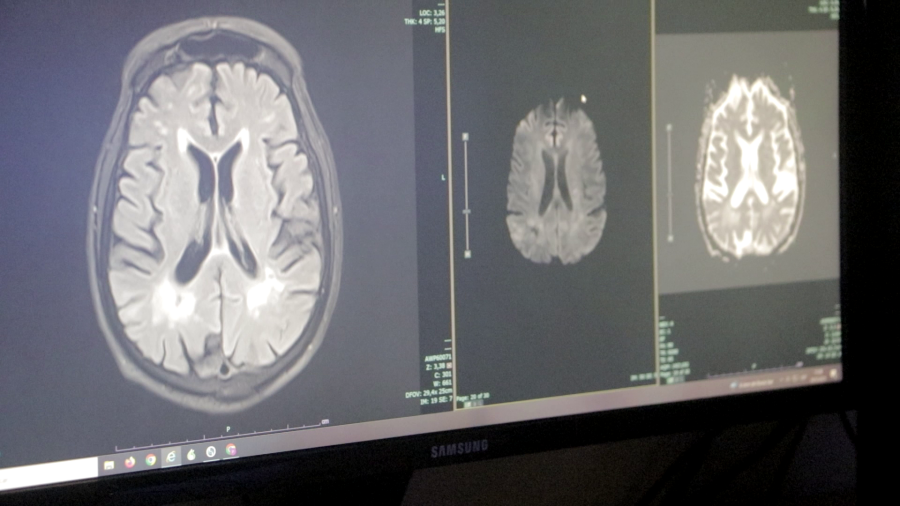

Durante el año, el servicio logró dar respuesta a un amplio abanico de patologías neurológicas de alta complejidad, incluyendo cuadros vasculares, tumorales y emergencias neuroquirúrgicas, consolidando al Parque de la Salud como centro de referencia regional.

En el área de emergentología, el servicio tuvo una fuerte intervención durante 2025, principalmente en casos de traumatismos de cráneo derivados de accidentes.

“Se pudo resolver la gran mayoría de los traumatismos de cráneo, siempre con el apoyo fundamental de los servicios de terapia intensiva y anestesia”, remarcó el Jefe del Servicio.